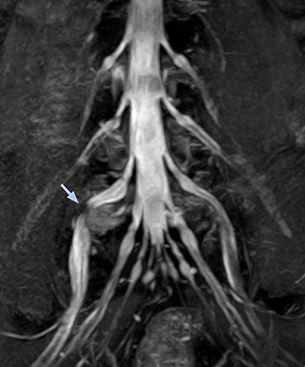

“In patients with lower extremity neurological symptoms, NerveVIEW helps us to determine the disease matching the patient’s symptoms by directly visualizing the nerves. We use the sequence mainly, when there is suspicion of intraforaminal stenosis, extraforaminal stenosis or lateral disc herniation, which is often based on routine T2- and T1-weighted images. Additionally, the excellent depiction of the course of nerves makes NerveVIEW a good navigator when applying treatment such as block therapy or surgery.”

“Although symptoms of typical disc herniation and atypical hernia are very similar, the actual site of herniation is different. It is therefore important to characterize the nerve’s condition both inside and outside of the intervertebral foramina. “Conversely, if we see no abnormality in NerveVIEW, we can assume at least that there is no severe condition that requires surgery. Like this, it can help us avoid unnecessary surgery. NerveVIEW can have a tremendous impact in this way.”

“NerveVIEW is really useful for those cases where a nerve disorder is strongly suspected based on the clinical examination but our regular MRI images do not show any findings. These atypical herniations and spinal canal stenosis, occurring in 5% to 15% of the total lumbar herniation/stenosis cases are our main target when using NerveVIEW,” says Dr. Yabuki.

“NerveVIEW can clearly show nerve courses and presence of nerve compression. However, when multiple abnormalities are seen, it can still be hard to determine which nerve is causing the symptoms,” says Dr. Yabuki. “In our experience so far, we see abnormal findings on NerveVIEW in about 70% of elderly patients. As the pain is usually caused by only one nerve, we thus need to find the exact corresponding nerve.” “With a nerve root block, the patient's pain is improved by infiltration of local anesthesia directly around the nerve root considered to be responsible. Knowing such nerve root block findings prior to image interpretation, helps to easily recognize abnormal findings on NerveVIEW as well. In other words, without a priori knowledge, based on symptoms and/or nerve root block findings, we must be aware of the possibility of overdiagnosis.”